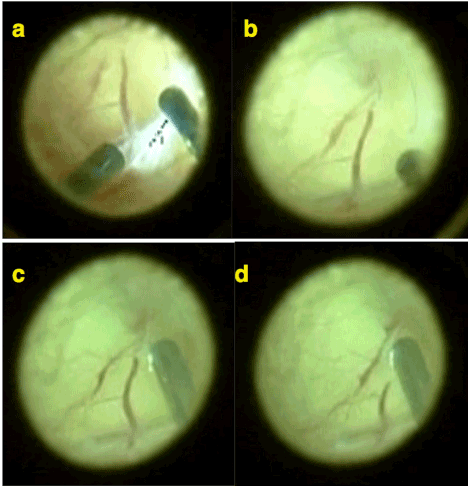

For study eyes a limited laser treatment with dense laser spots completely covering the demarcation line (stage II /III) 360 degrees around 5-6 rows extending to both vascular and avascular sides by leaving the most of peripheral avascular retina free of laser was performed (Figure 2-3). Fellow control eyes got a standard pan-avascular-retinal laser treatment.

During follow up period 3/68 (4.41%) study eyes developed a secondary demarcation line and without a need for laser treatment it regressed spontaneously and retinal vascularization completed without any further complication (Figure 2-3).

Figure 2. a) Stage 3 ROP with plus disease. Note the (neo) vascularizations extend as normal continuation of retinal vessels. b) Limited laser treatment of stage 3 area by white (fresh) laser spots extending over both vascular and avascular sides of demarcation but leaving most of peripheral avascular retina free of laser. c) 1 week after the limited laser treatment. A limited intravitreal hemorrhage occurred and proliferations and plus disease are regressed. d) 3 weeks after the laser treatment. Laser spots became more pigmented and the disease is totally regressed.